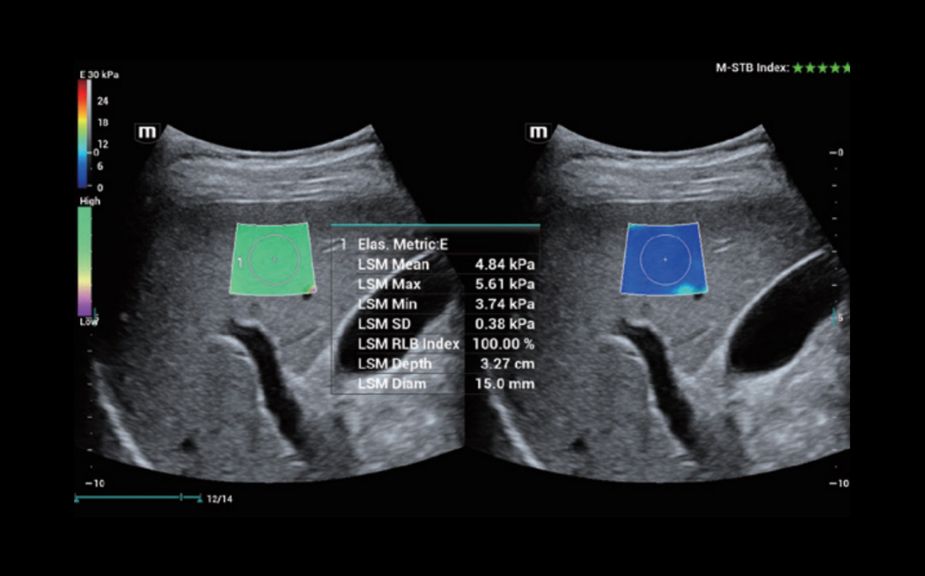

–î–Η–Α–≥–Ϋ–Ψ―¹―²–Η–Κ–Α –Ψ―΅–Α–≥–Ψ–≤―΄―Ö –Ω–Ψ―Ä–Α–Ε–Β–Ϋ–Η–Ι ―¹ –Ω–Ψ–Φ–Ψ―â―¨―é –Κ–Ψ–Ϋ―²―Ä–Α―¹―²–Ψ–≤: –Κ–Ψ–Ϋ―²―Ä–Α―¹―²-―É―¹–Η–Μ–Β–Ϋ–Ϋ–Α―è –≤–Η–Ζ―É–Α–Μ–Η–Ζ–Α―Ü–Η―è UWN+

–‰―¹–Ω–Ψ–Μ―¨–Ζ–Ψ–≤–Α–Ϋ–Η–Β –Κ–Α–Κ –≤―²–Ψ―Ä–Ψ–Ι –≥–Α―Ä–Φ–Ψ–Ϋ–Η–Κ–Η, ―²–Α–Κ –Η –Ϋ–Β–Μ–Η–Ϋ–Β–Ι–Ϋ―΄―Ö ―³―É–Ϋ–¥–Α–Φ–Β–Ϋ―²–Α–Μ―¨–Ϋ―΄―Ö ―¹–Η–≥–Ϋ–Α–Μ–Ψ–≤

–£―΄―¹–Ψ–Κ–Α―è ―΅―É–≤―¹―²–≤–Η―²–Β–Μ―¨–Ϋ–Ψ―¹―²―¨ –Κ –Ϋ–Η–Ζ–Κ–Ψ–Α–Φ–Ω–Μ–Η―²―É–¥–Ϋ―΄–Φ ―¹–Η–≥–Ϋ–Α–Μ–Α–Φ –Η –±–Ψ–Μ―¨―à–Β–Β –≤―Ä–Β–Φ―è –Ω–Β―Ä―¹–Η―¹―²–Β–Ϋ―Ü–Η–Η –Κ–Ψ–Ϋ―²―Ä–Α―¹―²–Ϋ–Ψ–≥–Ψ –≤–Β―â–Β―¹―²–≤–Α

–ö–Θ–Θ–½–‰: –Φ–Β―²–Α―¹―²–Α―²–Η―΅–Β―¹–Κ–Η–Ι ―Ä–Α–Κ –Ω–Β―΅–Β–Ϋ–Η

–ö–Θ–Θ–½–‰: –Ω–Β―Ä―³―É–Ζ–Η―è –Α–¥–Β–Ϋ–Ψ–Φ―΄ ―â–Η―²–Ψ–≤–Η–¥–Ϋ–Ψ–Ι –Ε–Β–Μ–Β–Ζ―΄